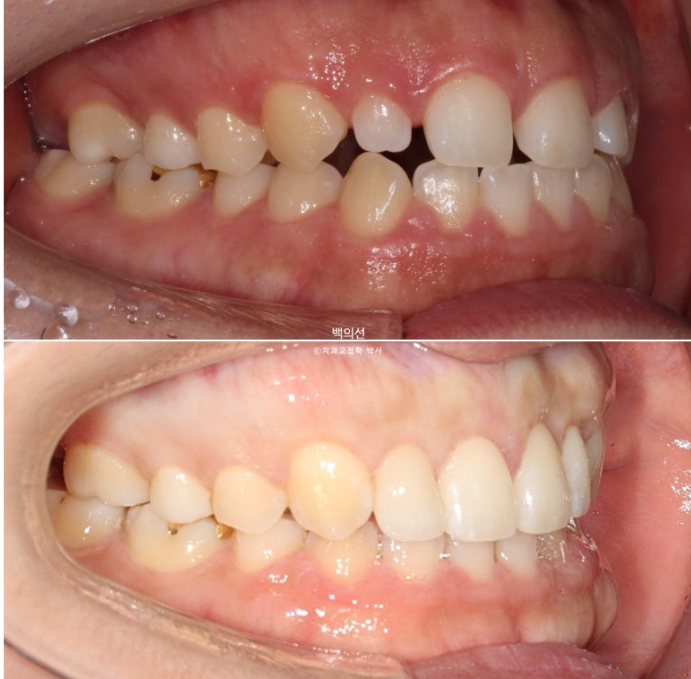

아래턱이 좌측으로 틀어져 있는 골격적 비대칭이 있고 앞니 중심선도 어긋나 있습니다.

파란화살표는 왜소치 입니다.

교정 후 라미미네이트 수복이 필요합니다.

위 앞니가 아래 앞니를 덮지 못하는 개방교합이 보입니다.

교합면에서 보면 안쪽 맨 뒤 큰어금니 하나가 없는 것이 보입니다.

선천적 결손치아 입니다.

적극적인 돌출 해소를 위해 작은어금니 4개 발치가 필요한 상황입니다.

하지만 큰어금니가 결손된 쪽은 작은어금니 발치 없이 후방이동으로 균형을 맞추기로 합니다.

클리피씨 교정을 선택하셨고 작은어금니 3개를 발치 후 치료에 들어갔습니다.

치료 시작 1년째 사진입니다.

24.07

발치공간 폐쇄, 앞니 후방이동, 거미스마일 해소와 하관길이 및 무턱의 해소를 위한 전체치열 함입을 진행합니다.